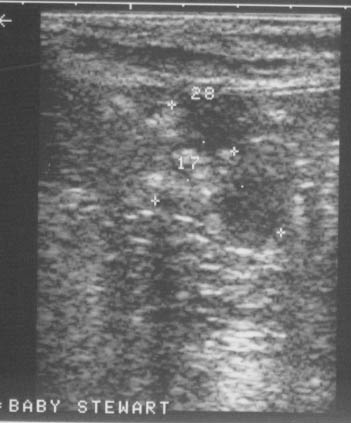

At this time "Baby" was eating and acting normal. My vet recommended starting Piroxicam therapy. Piroxicam is the drug "Feldene" and was initially used as a arthritis drug in humans. The dosage for a dog has to be calculated per weight and my vet had the prescription for my beagle "compounded" (or specially made at a compounding pharmacy). It was about 12.00 per month for treatment. The drug can upset the stomach so I had to give it to her with the evening feeding. It is given once a day everyday.Baby's tumor was found in August 2003. In March 2004 a repeat Ultrasound was done and dramatic reduction of tumor size was noted. (see pictures) 2003 is the first one-see the round object. 2004 is second picture.